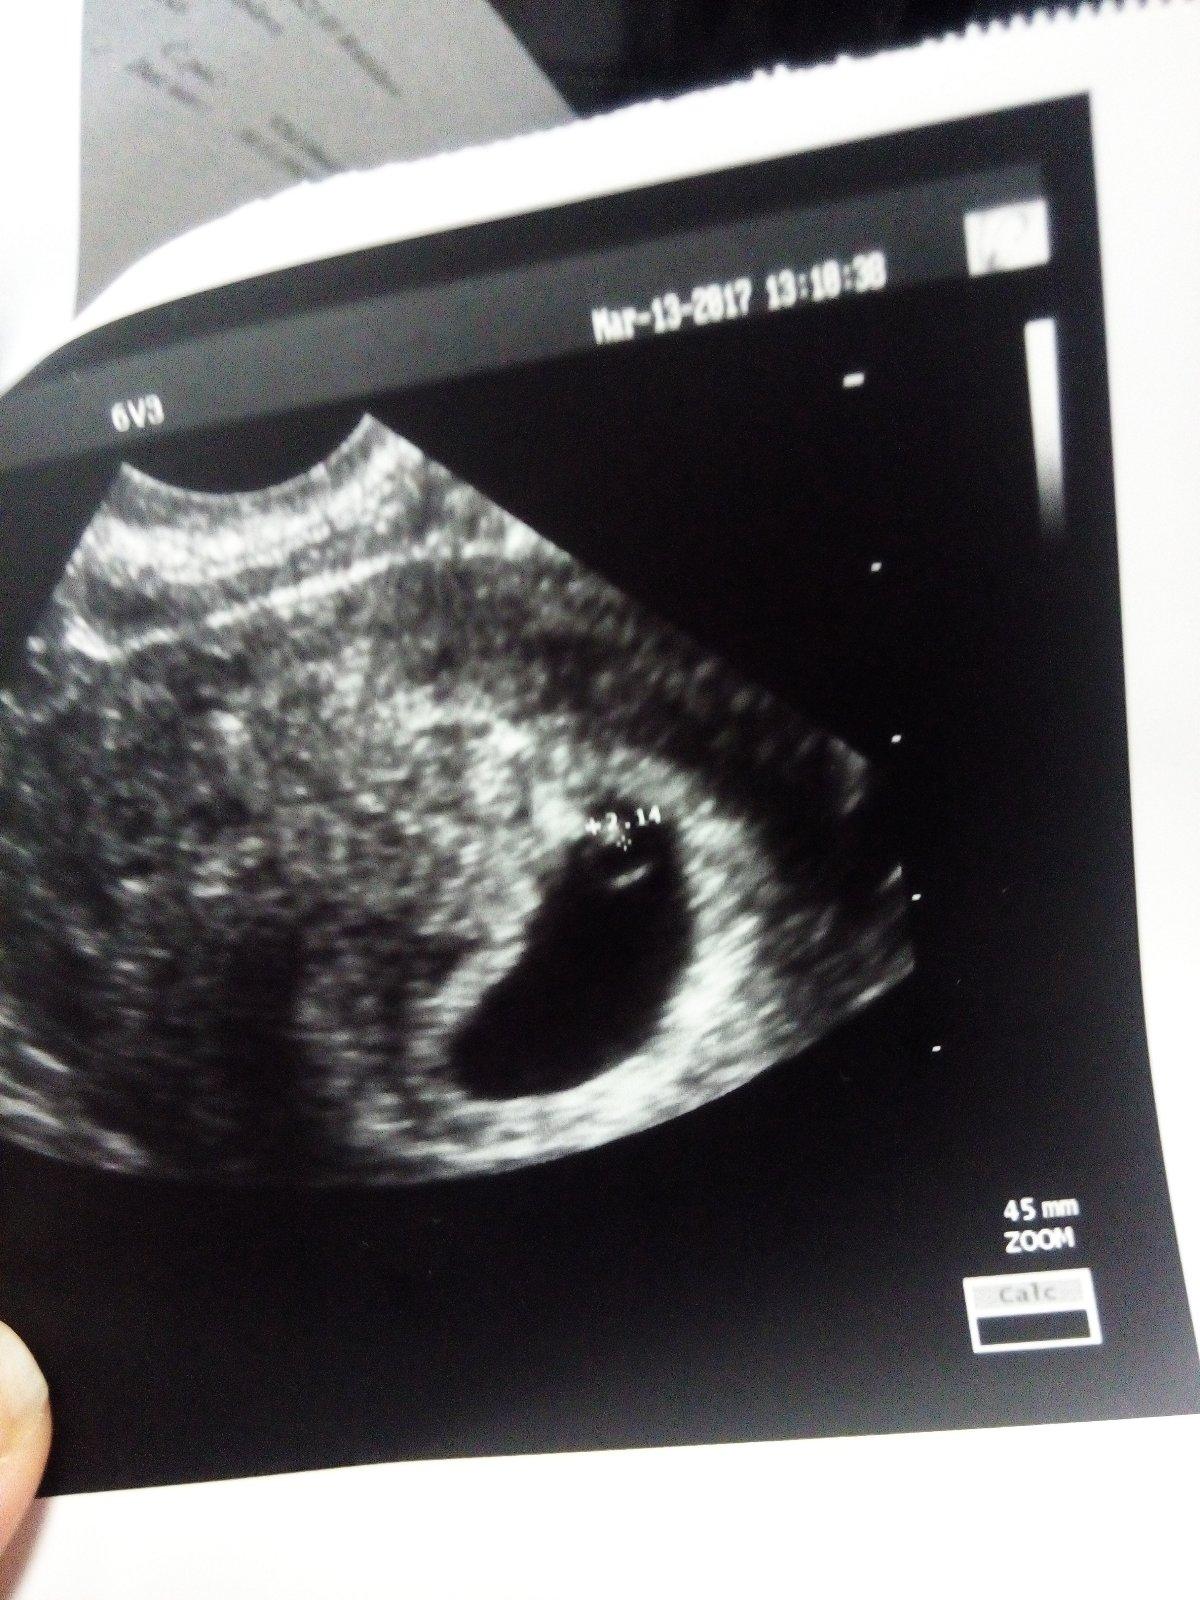

@ikonica ahoj 🙂 tak rastieme sme 18 tt podla ultrazvuku uz. Aj ked som krvacala, teraz spinim. Bola som v nemocnici ale vsetko je v poriadku babatko ma len strasi. Potmehut to je. Citim ale vnutorne ze je vsetko ok aj doktori viaceri ma vysetrili ze vsetko ok. Ze sa to stava niekedy. 29. 3 ideme na velke sono 🙂